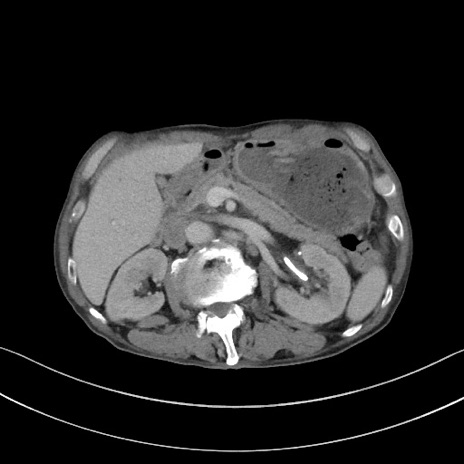

症例3(横断像)

【症例】 70歳代男性

【主訴】右鼠径部腫瘤、疼痛

【現病歴】本日朝より上記主訴あり、受診。

【既往歴】膀胱癌にて膀胱全摘、両側尿管皮膚瘻

【データ】WBC 5600、CRP 0.56